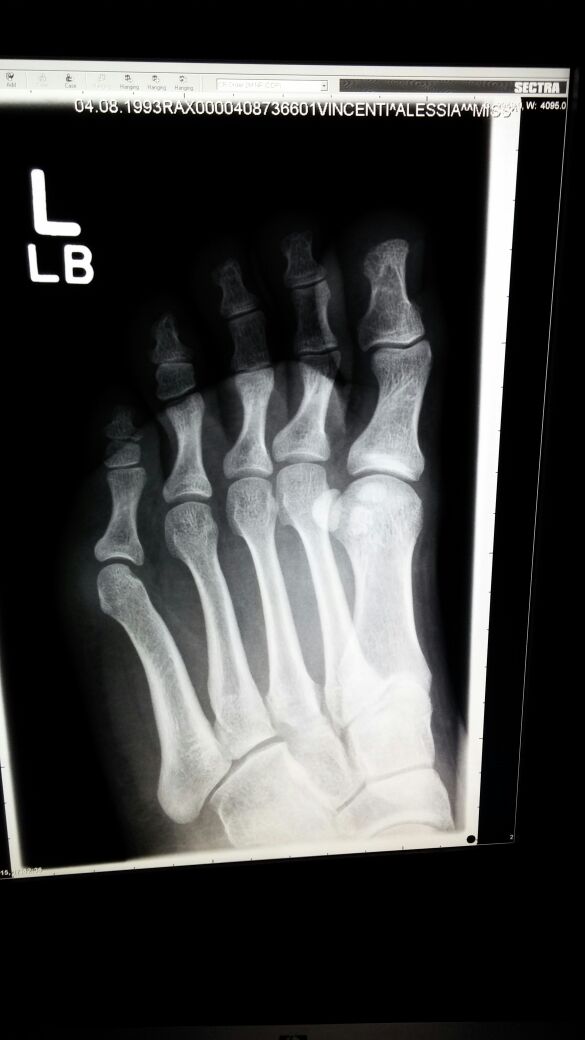

Sono una ragazza di 22 anni. 2 settimane fa ho riscontrato un problema sotto la pianta del piede SX..mi sono alzata una mattina con il piede gonfio. Mentre camminavo mi faceva male. Dopo 3 giorni ho notato che il dolore continuava, sono andata a farmi i raggi. Mi hanno riscontrato un infiammazione dei tessuti molli con successiva visita di uno specialista. In allegato i raggi X.

tmp_4514-IMG-20150202-WA00121413360518.jpg

[ 44.48 KiB | Osservato 4471 volte ]

dalla sua breve descrizione sembrerebbe trattarsi di una fascite plantare.